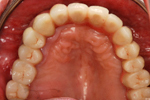

① 上の顎・治療前

③ 上の顎 インプラント後

④ 上の顎。最終的なオールセラミックの歯が入ったところ。

⑤ 上下とも治療の終わった状態。メインテナンスに入ります。

60才代 女性

総額:360万円(税別)

治療期間:約1年

リスク副作用:経年的な骨の吸収。セラミックの破損。